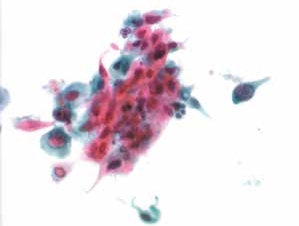

2. 非角化型鳞状细胞癌(non-keratinized squamous cell carcinoma)(图4-65~4-70)

图4-65 非角化型鳞癌(高倍、液基、巴氏染色)

明显的肿瘤素质,癌细胞成团,形态多样,核大,深染,染色质粗颗粒状,胞质蓝染。